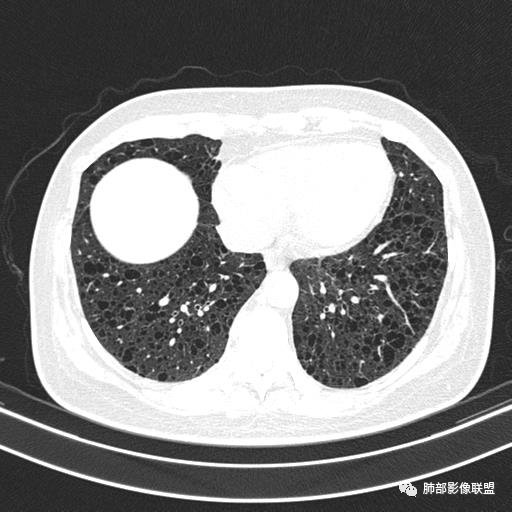

双肺弥漫囊腔,累及肋膈角,囊腔形态相对规则单一。

CT平扫示双肺弥漫分布大小不等囊状薄壁透光区,无内、中、外带分布差异,间质稍示增厚。拟LAM

中年女性育龄期妇女,咳嗽气喘,无吸烟史,有苯吸入史。影像:双肺弥漫均匀小囊腔,无明显分布优势,囊腔形态欠规则,壁薄,部分囊腔边缘血管征,伴双肺弥漫磨玻璃影,无结节,考虑lam,鉴别苯中毒肺损伤,囊腔多有分布优势,小叶中心分布为主,形态规整等

CT表现:双肺弥漫大小不等的薄壁囊腔,囊壁<2mm,外形规则,血管影多位于囊腔周围,囊腔之间肺组织正常,随着疾病进展到晚期,囊腔变大、增多,不可胜数,囊腔可融合成较大的囊,与肺气肿相似,形成间质性肺纤维化。部分病例可出现结节影。